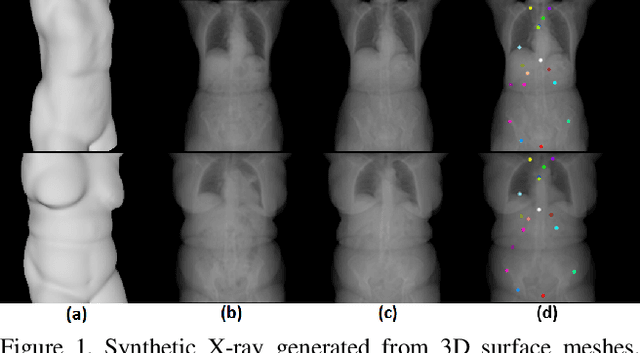

Abstract:We present a novel framework that learns to predict human anatomy from body surface. Specifically, our approach generates a synthetic X-ray image of a person only from the person's surface geometry. Furthermore, the synthetic X-ray image is parametrized and can be manipulated by adjusting a set of body markers which are also generated during the X-ray image prediction. With the proposed framework, multiple synthetic X-ray images can easily be generated by varying surface geometry. By perturbing the parameters, several additional synthetic X-ray images can be generated from the same surface geometry. As a result, our approach offers a potential to overcome the training data barrier in the medical domain. This capability is achieved by learning a pair of networks - one learns to generate the full image from the partial image and a set of parameters, and the other learns to estimate the parameters given the full image. During training, the two networks are trained iteratively such that they would converge to a solution where the predicted parameters and the full image are consistent with each other. In addition to medical data enrichment, our framework can also be used for image completion as well as anomaly detection.